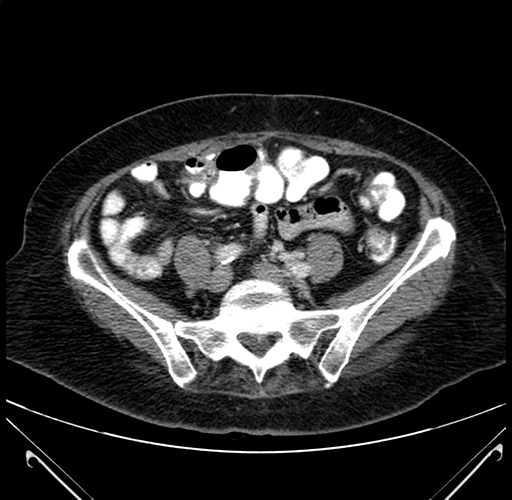

Axial Venous